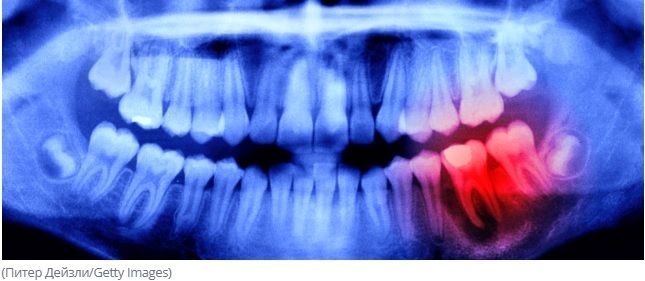

Было проведено исследование, чтобы выяснить, могут ли такие проблемы с полостью рта, как пародонтит (заболевание дёсен) и потеря зубов повышать риск нейродегенеративных заболеваний, таких как инсульт, болезнь Альцгеймера и другие формы деменции.

Результаты оказались однозначными: обе проблемы связаны с более быстрой атрофией гиппокампа — части мозга, отвечающей за память, обучение и эмоции. Это важный результат, однако подобная связь была выявлена уже не в первый раз.